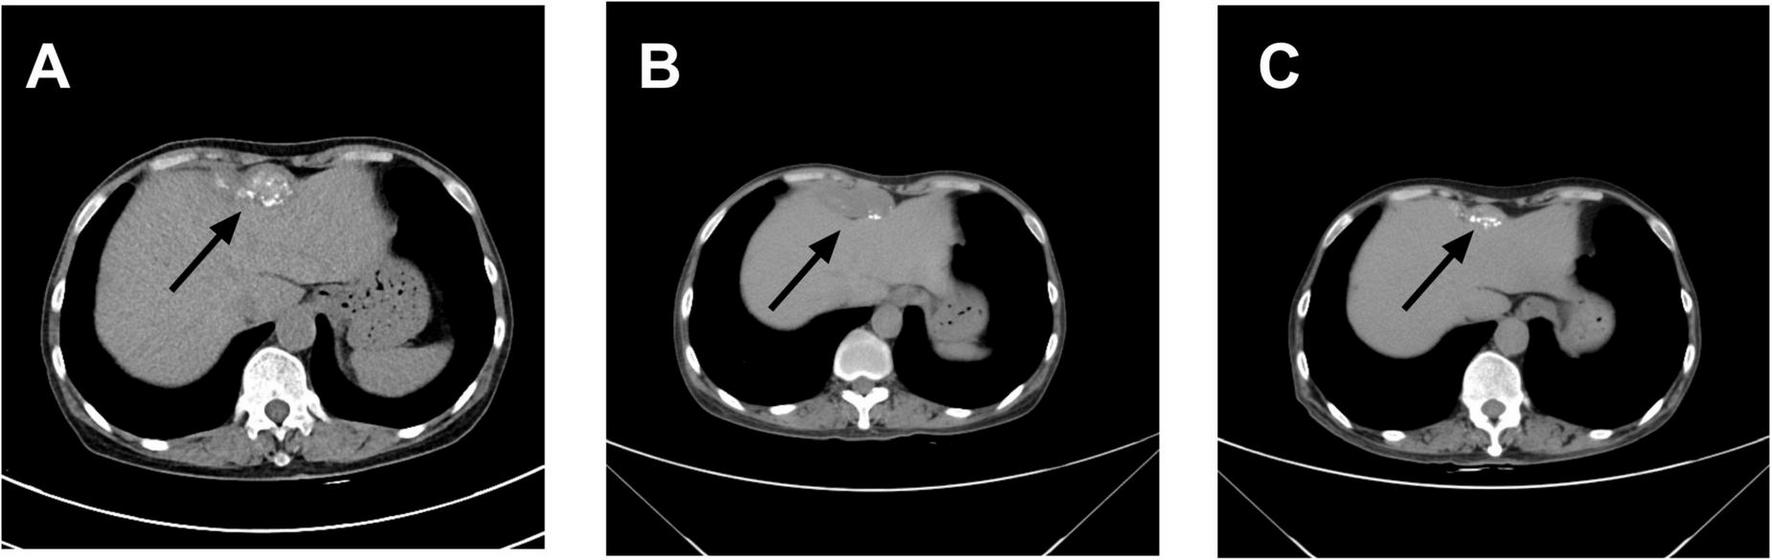

Contrast-enhanced abdominal CT (Figure 1) revealed an irregular soft-tissue density lesion (approximately 5.2 × 2.3 × 6.2 cm) anterior to the liver, accompanied by a 1.5 cm nodule in the left peritoneal cavity, raising suspicion of malignancy. Subsequent PET-CT (Figure 2) confirmed multiple FDG-avid peritoneal nodules and masses, with a maximum standardized uptake value (SUV∼max∼) of 7.1, further supporting the suspicion of metastatic disease. Blood and urine cultures showed no growth.

FIGURE 1

Changes in abdominal mass observed on computed tomography (CT): (A) On April 8, 2023, contrast-enhanced abdominal CT revealed an irregular soft tissue density lesion anterior to the liver, measuring 5.2 × 2.3 × 6.2 cm. A small lymph node (∼1.5 cm) was noted at the level of the umbilicus in the left abdominal cavity, with a consideration of malignant tumor. (B) On March 15, 2024, contrast-enhanced abdominal CT demonstrated a calcified mass anterior to the liver (5.1 × 2.0 × 3.6 cm) and a small lymph node (∼0.8 × 0.8 cm) at the same level within the left abdominal cavity, with a differential diagnosis of abdominal tuberculosis. (C) On October 30, 2024, contrast-enhanced abdominal CT showed a smaller anterior hepatic mass with calcification (3.9 × 1.3 cm). The lymph node at the umbilical level in the left abdominal cavity remained unchanged (∼0.8 × 0.8 cm). Arrows indicate the lesion locations.

However, after completing 1 year of anti-tuberculosis therapy, the patient was re-admitted on March 15, 2024, due to recurrent low-grade fever. Repeat abdominal CT (Figure 1) showed progression of the hepatic lesion (now 5.1 × 2.0 × 3.6 cm) and persistent peritoneal thickening. Transesophageal echocardiography (TEE) revealed vegetations on the mitral valve (Figure 4), compatible with infective endocarditis.

As of June 2025 (14 months post-treatment initiation), the patient remained symptom-free, with no recurrent fever, myalgia, or fatigue. A follow-up abdominal CT on October 30, 2024, showed significant reduction of the Intra-abdominal lesion to approximately 3.9 × 1.8 × 1.2 cm and marked resolution of peritoneal thickening, confirming effective treatment (Figure 1). She continues regular outpatient follow-up, maintaining good mental health and nutritional status, with no signs of disease recurrence.

In this case, the initial whole-abdomen enhanced CT scan revealed a hepatic anterior mass and multiple intra-abdominal nodules. Subsequent PET-CT demonstrated multiple FDG-avid lesions in the peritoneum, with a maximum standardized uptake value (SUVmax) of 7.1. These imaging features closely mimicked malignant neoplasms, particularly peritoneal metastases. Literature suggests that 18F-FDG PET/CT can detect focal hypermetabolism on cardiac valves or vascular walls, facilitating diagnosis of infectious endocarditis and vascular infections in chronic Q fever (15). This modality improves diagnostic accuracy when incorporated into the Duke criteria and helps localize sites of chronic Q fever infection (16, 17). In the present case, however, PET-CT demonstrated increased metabolic activity initially suggestive of multifocal metastatic malignancy rather than Q fever. Subsequent percutaneous biopsy revealed only basophilic amorphous material and granulomatous inflammation with negative acid-fast staining. These non-specific findings provided no definitive microbiological evidence and led to the initial misdiagnosis of tuberculous peritonitis.